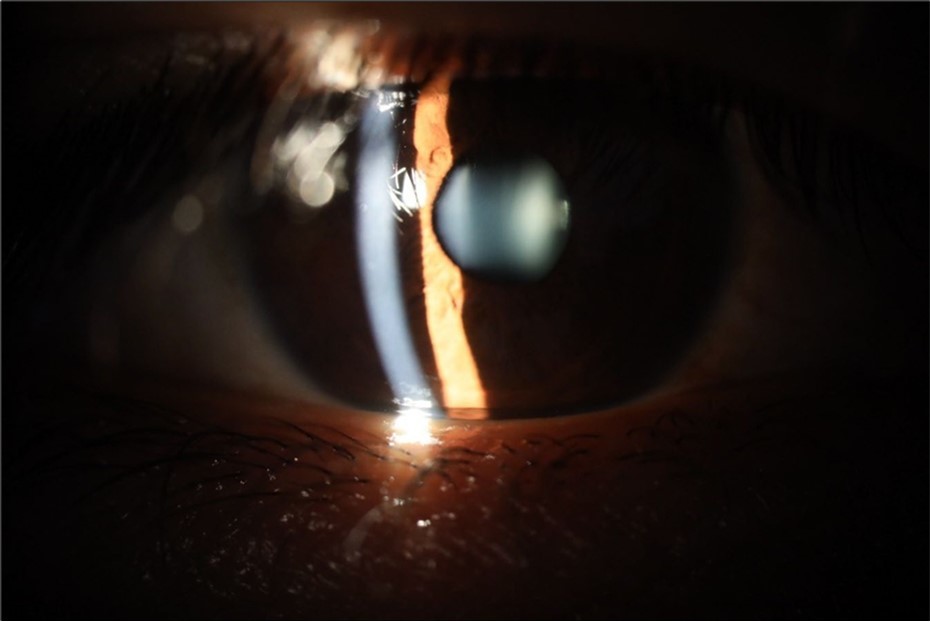

Figure 5.The slit-lamp photograph shows the anterior segment, relatively unscathed, in terms of transparent media (Cornea, crystalline and vitreous).

Figure 15.The photograph shows better specular reflection, compared to the first day of the exam.

Figure 16.The anterior segment of the right eye shows the vitreous with greater transparency. The cornea and lens, as well as the anterior chamber, are in good condition.

Figure 20.The mirror reflection of the affected (right) eye continues to improve.

Figure 21.The anterior segment of the right eye responds with difficulty to mydriatics, which is usual in diseased eyes.

Figure 25.Mirror reflection of the affected eye (right side), with good appearance. This indicates that the transparent media of the eyeball (Cornea, anterior chamber, lens, and vitreous) are in good condition.

Figure 26.The macrograph of the anterior segment of the right eye (affected) shows very good transparency of the cornea, anterior chamber, lens, and vitreous.